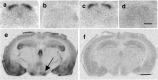

Figure 6.

Autoradiographic localization of specific 125I-OTA binding sites in mouse brain and spinal cord. In WT (a) and V1AR KO mice (c), OTR binding is dense in all superficial laminae of the lumbar spinal cord. OTR binding is absent in OTR KO mice (d). In WT mice, OTR binding is dense in the ventromedial hypothalamus (e, arrow). OTR binding is displaced by coincubation of radioligand with 2 μm cold OXT (b, f). Scale bars: d, 500 μm; f, 1500 μm.